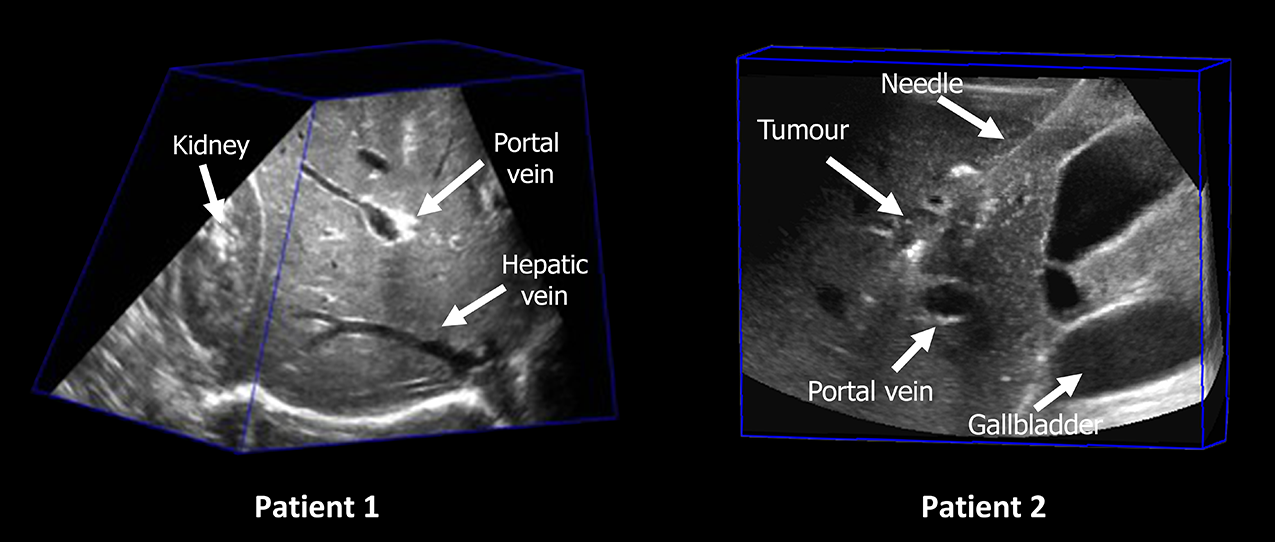

Figure 3. 3D US examples of two patients.

Figure 3 presents a patient’s acquired 3D US images, demonstrating the 3DLIVUS system in action. Relevant anatomical structures—including hepatic vessels, kidney, gallbladder, tumour, and inserted needles—are clearly visualized in the reconstructed volume. This achievement provides a critical foundation for subsequent investigations in percutaneous liver tumour ablation, including intra-procedural tumour coverage assessment, enhanced tumour identification, and needle tracking (see details below).